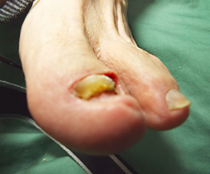

巻き爪、タコ、魚の目等があると症例に示すように、様々な症状を呈します。

早いうちに処置をして快適な生活を心がけましょう。